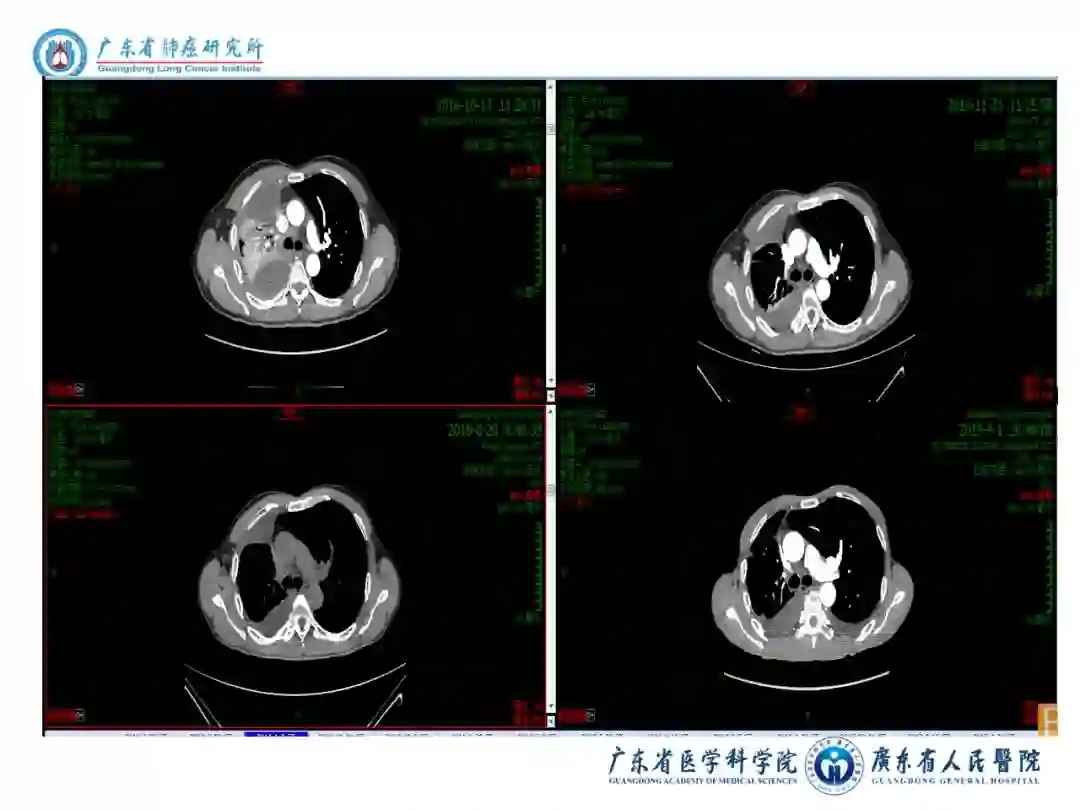

图表资料